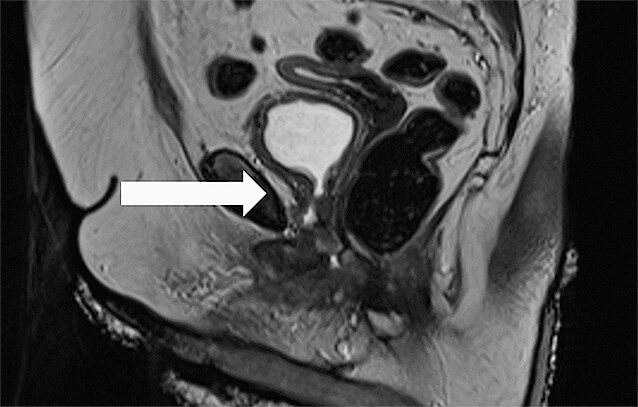

Nach erneuter Tumorboardbesprechung führten wir 01/2022 den Versuch einer TUR-Komplettresektion (40 g Resektatgewicht) durch. Histologisch ergab sich diesmal ein Tumor vom Müllerischen Typ im Sinne eines klarzelligen Karzinoms (ehemals mesonephrisches Adenokarzinom) pT1 pNx V0 L0 Pn0 RX. Eine MRT 03/2022 wies noch einen minimalen lokalen Restbefund nach (▶ Abb. 3).

Der darüber hinaus vorbeschriebene suspekte Lymphknoten vaginal links war allenfalls noch fraglich nachzuweisen. Insgesamt konnte in den folgenden -Untersuchungen eine Metastasierung ausgeschlossen werden. Die durch unser Tumorboard zwischenzeitlich empfohlene Exenteration wurde von der Patientin abgelehnt. Wir führten daraufhin 03/2022 eine nochmalige ausgedehnte transurethrale Nachresektion aus. Dabei bestätigte sich eine lokale Tumorfreiheit. Postoperativ wurde eine adjuvante Strahlentherapie mit insgesamt 45 Gy initiiert. Der ambulante Verdacht auf eine vesikovaginale Fistel konnte 11/2022 endoskopisch ausgeschlossen werden. Die Patientin befindet sich aktuell in regelmäßiger Tumornachsorge und ist bis dato rezidivfrei.